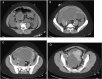

Case presentation: Here we describe a case of ruptured endometriomas in a 26-year-old nulligravid female with a history of heavy menses, progressive abdominal distension, and a recent urinary tract infection. The patient presented to the emergency department with upper abdominal pain radiating to her back with associated nausea. Computed tomography (CT) scan demonstrated diffuse ascites with a large, multilobulated, and multicystic septated mass arising in the right pelvis and extending into the lower abdomen. Findings were concerning for peritoneal carcinomatosis and the patient was admitted for evaluation. She developed progressive signs of sepsis and was emergently brought to the operating room for surgical exploration on hospital day (HD) number two. She was found to have ruptured pelvic cysts arising from both ovaries with diffuse contamination of the abdomen by cyst contents and bilateral salpingo-oophorectomy (BSO) was performed. Final pathology demonstrated benign bilateral endometriomas.

Clinical discussion: Endometrioma rupture is extremely rare and imaging findings may appear to represent disseminated peritoneal malignancy. CT findings demonstrating a pelvic mass with concurrent ascites should raise clinical suspicion for ruptured endometrioma, particularly in younger patients.